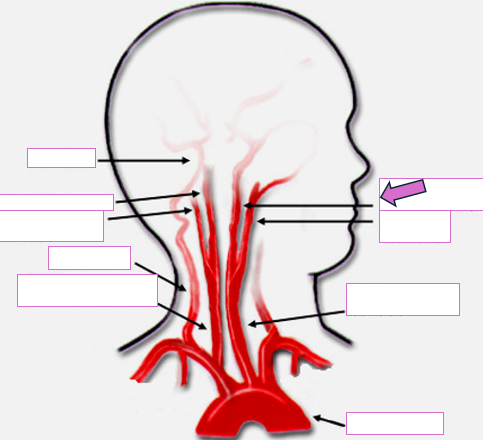

Based on the indicated area, identify this vessel

Brachiocephalic/innominate artery

Right subclavian artery

Right vertebral artery

Right carotid artery

Left carotid artery

Left vertebral artery

Left subclavian artery

Basilar

Right internal carotid

Right external carotid

Vertebral

Right common carotid

Left internal carotid

Left external carotid

Left common carotid

Aortic arch